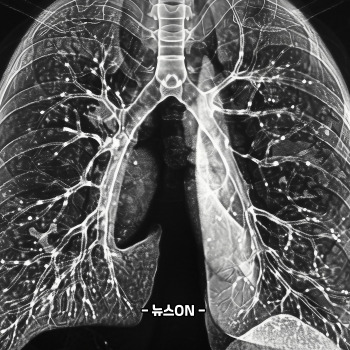

4) 폐암 진단 방법 7가지 — 조기 발견이 생존율을 바꾼다

폐암은 조기에만 발견해도 생존율이 2~4배 이상 달라질 수 있습니다. 다음은 실제 진단에 사용되는 7가지 방법입니다.

1. 저선량 흉부 CT(LDCT)

가장 중요한 검사입니다. 폐암 사망률을 최대 20~30%까지 낮춘다는 연구 결과가 있어 국가검진에도 포함돼 있습니다.